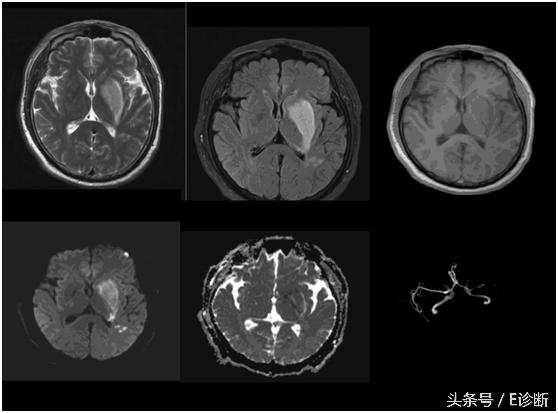

左侧额颞叶、基底节区超急性期脑梗死,发病2小时,T1WI、T2WI及flair像未见异常信号,DWI见高信号,ADC图为低信号,MRA示左侧大脑中动脉闭塞,右侧大脑中动脉狭窄。